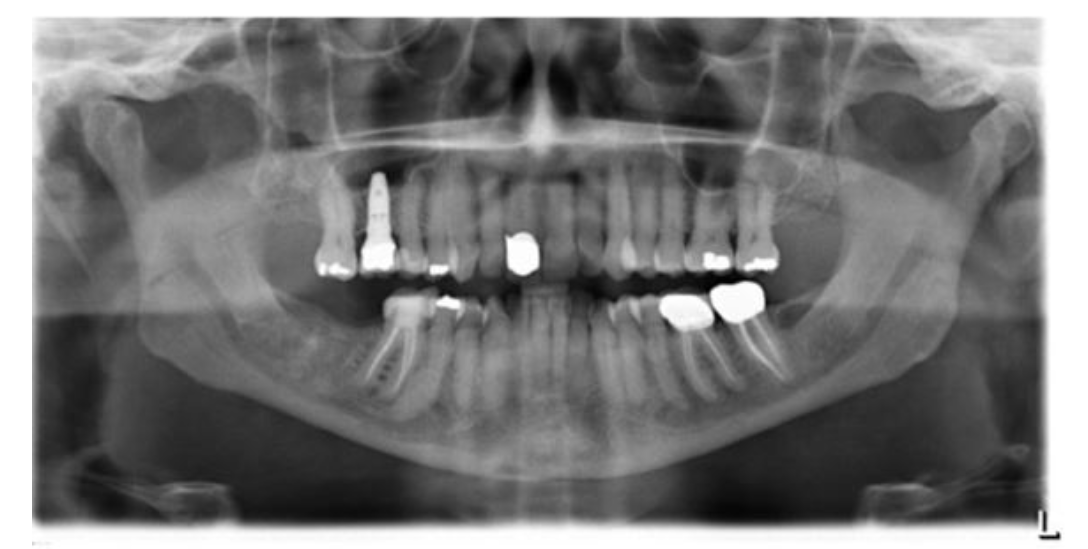

Mary Kay's Panoramic Image 2021, note the implant and some missing teeth.

Discover how Mary Kay overcame her TMJ pain and transformed her smile with the help of orthodontics and dental crowns. Follow her journey from jaw discomfort and cracked teeth to a beautiful, symmetrical smile after working with Dr. Elizabeth and Dr. DeVoe. Learn how her TMD symptoms improved, and see the stunning before-and-after results of her treatment.